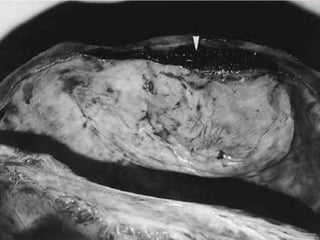

Late causes: Subendocardial Haemorrhage: Specially studied by Sheehan in 1930. Found in abortion, acute haemorrhage associated with pregnancy, and severe trauma. Well marked haemorrhages under endocardium of left ventricle. Flame shaped, confluent, non petecheal.  Causes of death due to injury:

Late causes: SubendocardialHaemorrhage: Specially studied by Sheehan in 1930. Found in abortion, acute haemorrhage associated with pregnancy, and severe trauma. Well marked haemorrhages under endocardium of left ventricle. Flame shaped, confluent, non petecheal. Causes of death due to injury: